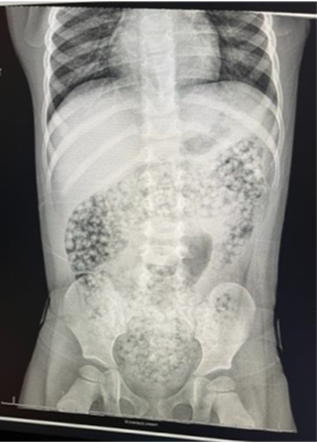

Water beads are also problematic in that because they are not metallic, they are more difficult to detect in x-rays, Pall noted.